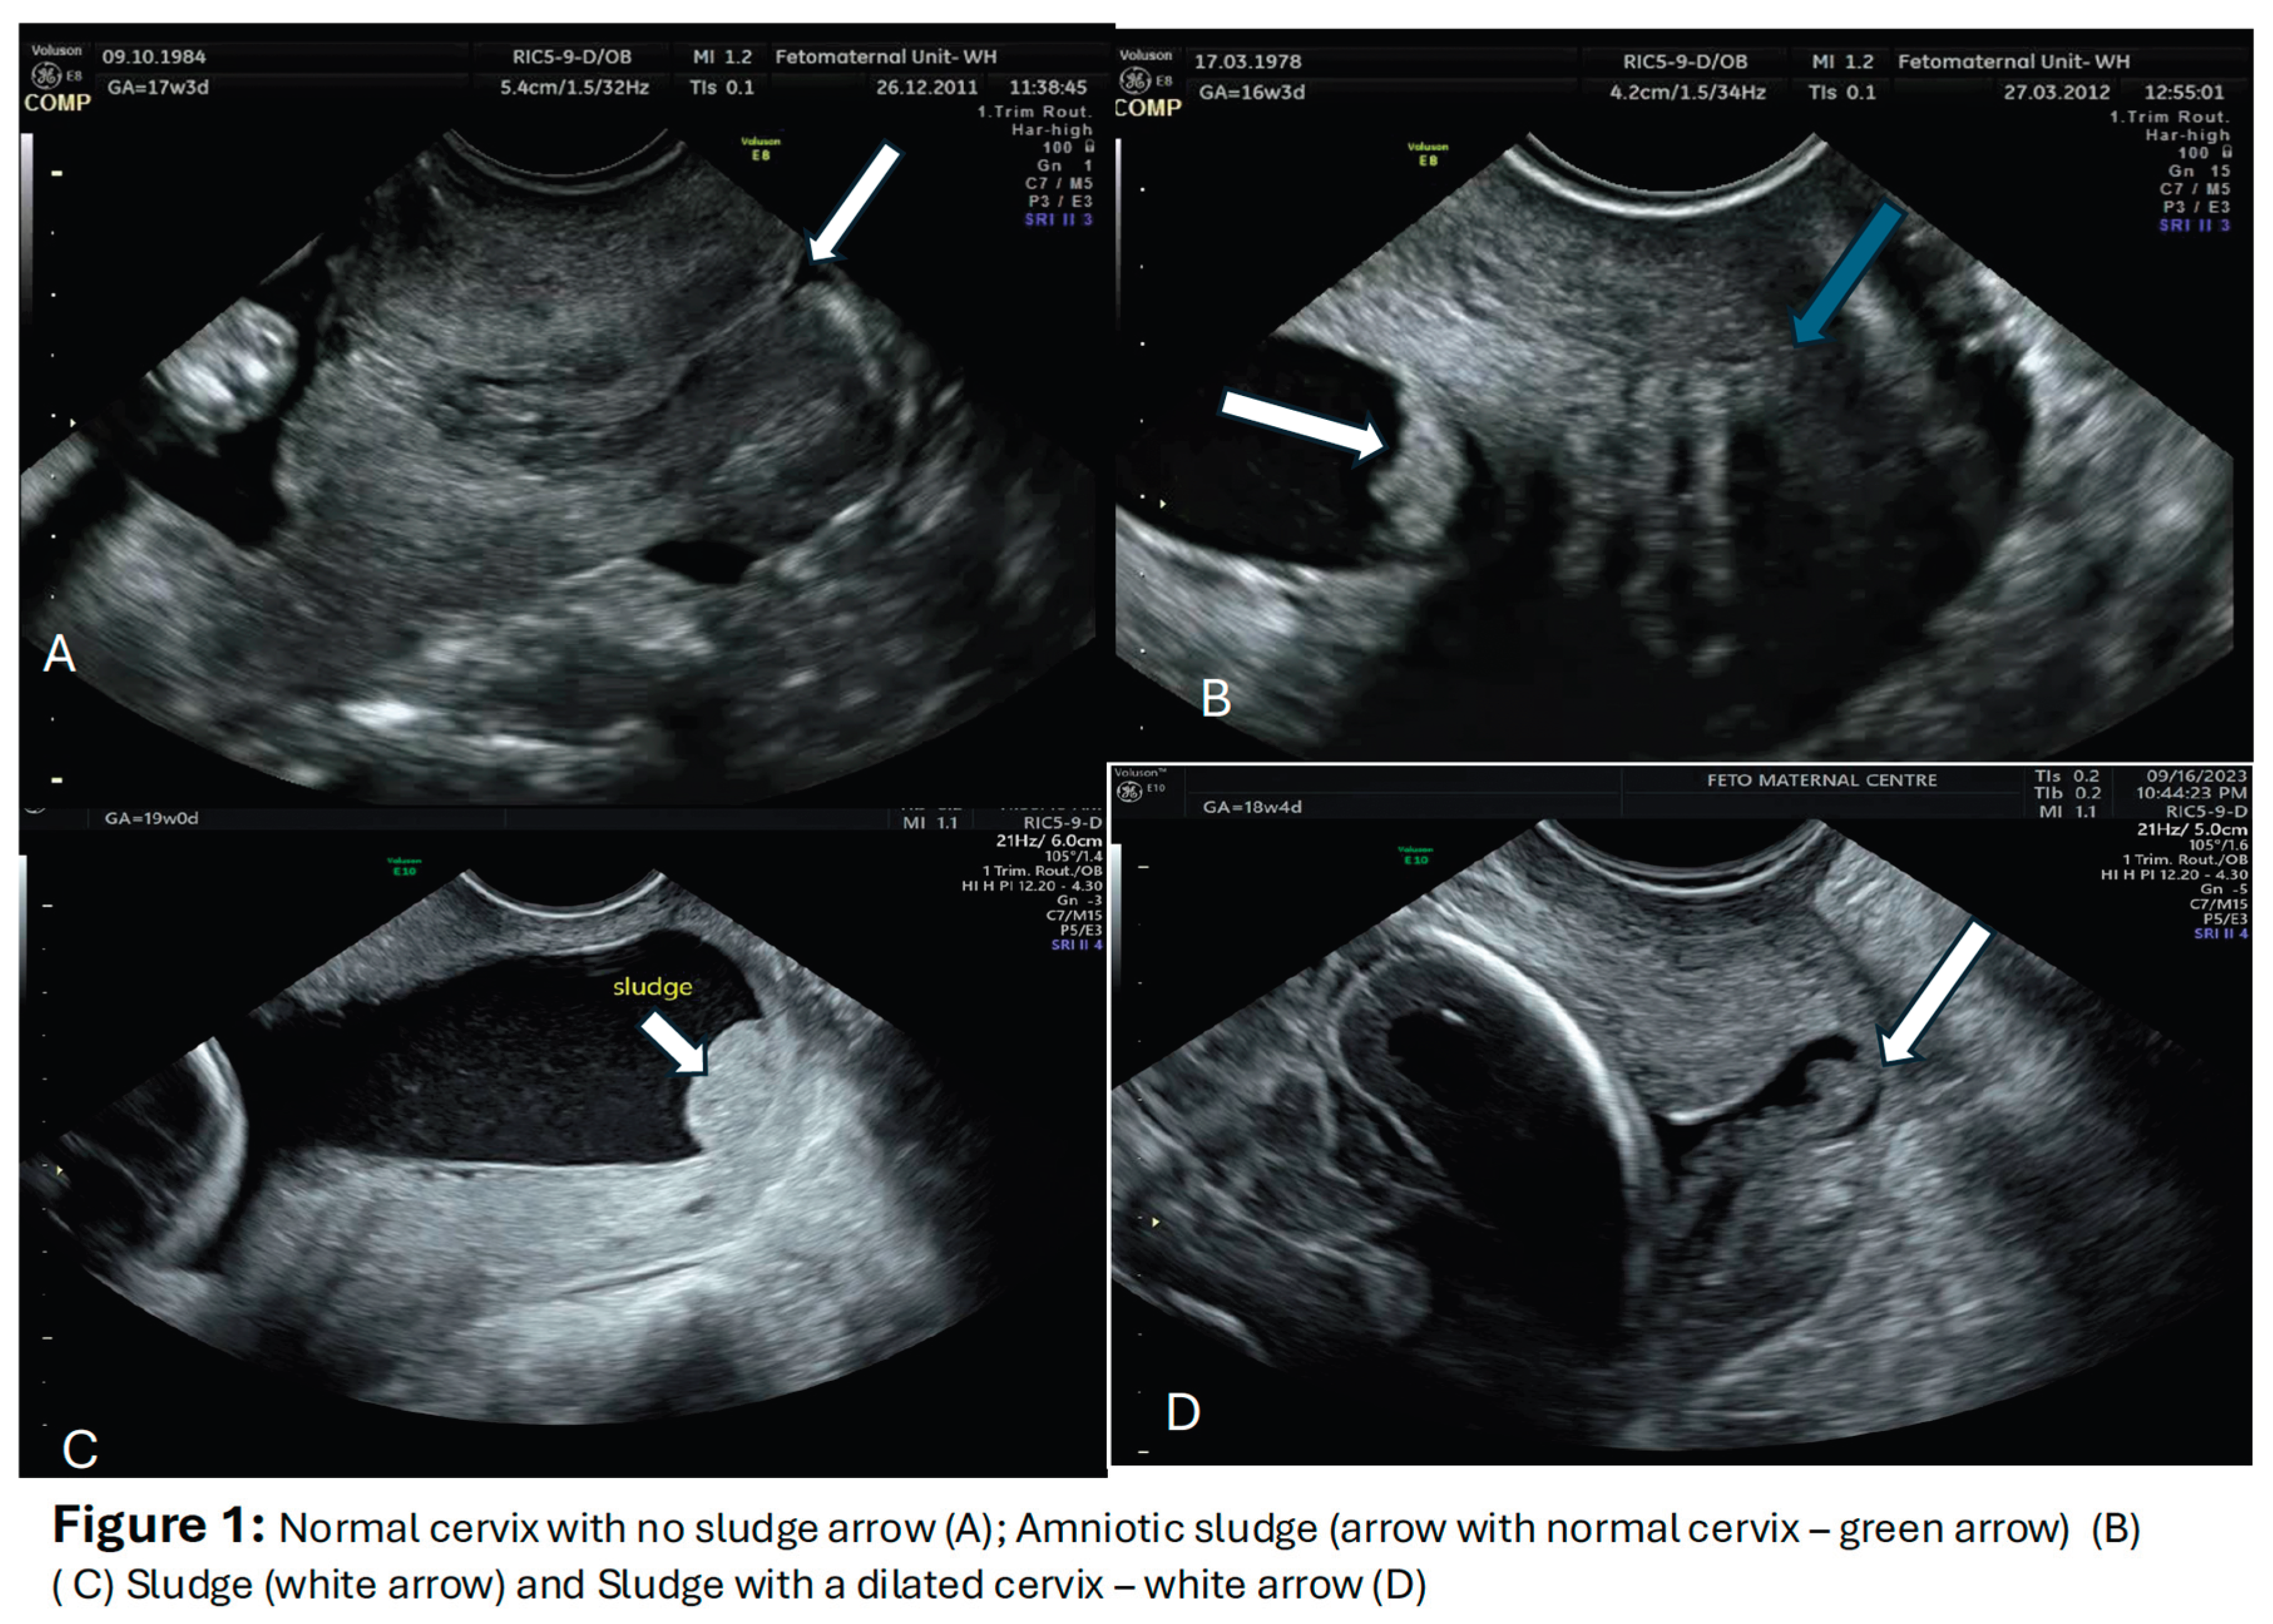

3. Imaging for the AF Sludge